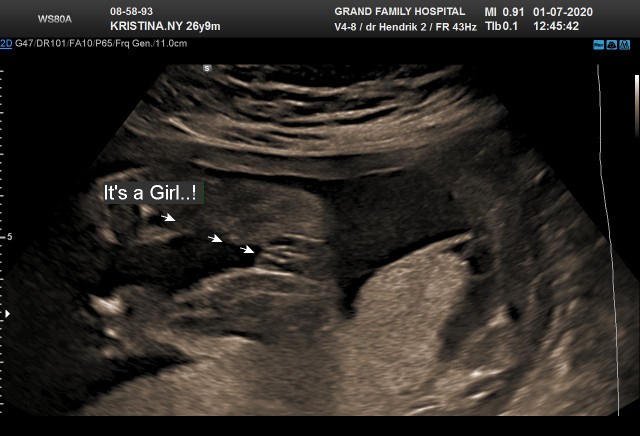

USG JK

Bun ini cewe / cowo yaa? Kata dokter sih cowo. Cuma masih penasaran aja sm penis nya yg mana hehe ๐ Barangkali bunda punya foto usg ttg jk yg jelas ..

Gondal gandilnya jelas bgt gtu haaa

Ini USG anak saya dlu bun, jk cowok.

cowok bun,

Monasnya dah jelas hihi

Kmrn pas usg 31week bun

Cowo bun ada salak ny

Aku cowok begini bun hehehe

Cwo..itu jk ny yg bulet..

Cowok itu biji nya hihi